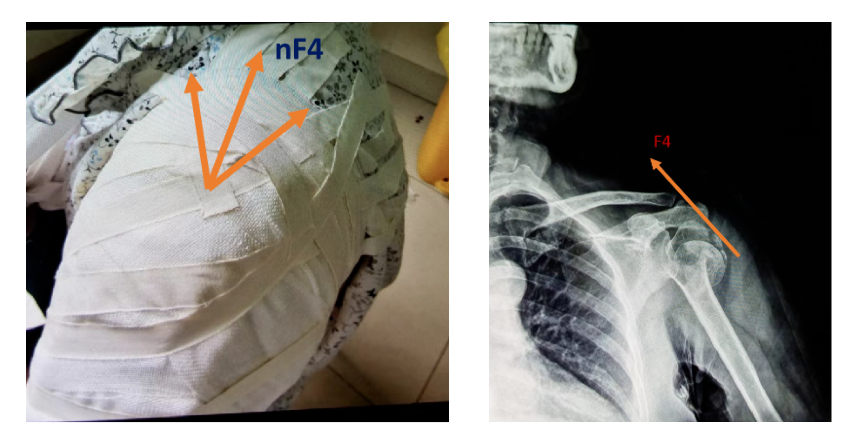

第三部分的力通过“胶布墙”制造的牵拉力nF4,力的方向指向颈肩部方向。这个力至关重要,假如一条胶布的牵拉力是100克,那么20条胶布组成的“胶布墙”就有2000g了。